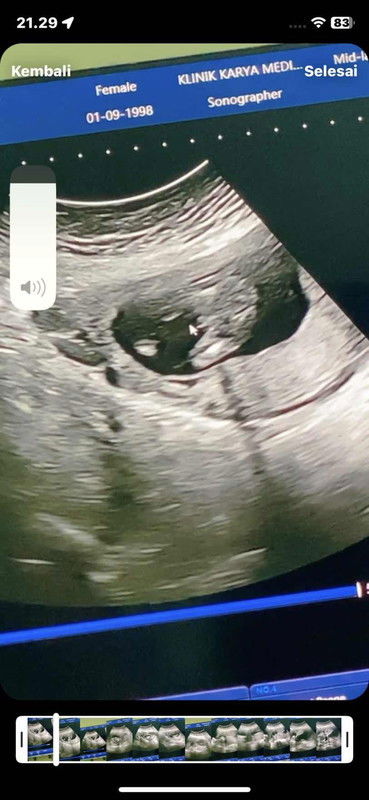

INI KELAMIN ATAU TALI PUSAR BUNDA2 CANTIK???

Halo bund kemarin usg usia 16 week, aku nanya jenis kelamin janinku. Terus bidan nya bilang saat USG "ini seperti monas kayaknya cowok, tapi liat lagi yah nanti 6 bulan takutnya ini tali pusar tapi kalau tali pusar sih seharusnya panjang ini enggak, semoga cowok ya bu" saya jadi bingung hehe... Sepengalaman bunda yg punya anak cowok, atau sepengelihatan bunda ini kelamin cowok Atau tali pusar yah xixi? Soalnya suami kepengen anak kedua ini cowok, doakan ya bund tp apapun jenis kelaminnya yg penting sehat 🥰 kalau keliahatannya ini beneran kelamin atau tali pusar yah bund? Ngobrol santai aja pgn tau pendapat yg lain 😇 semoga bunda2 disini sehat selalu AAMIIN#bantujawab #ingintahu #jenisKelamin #usg16minggu